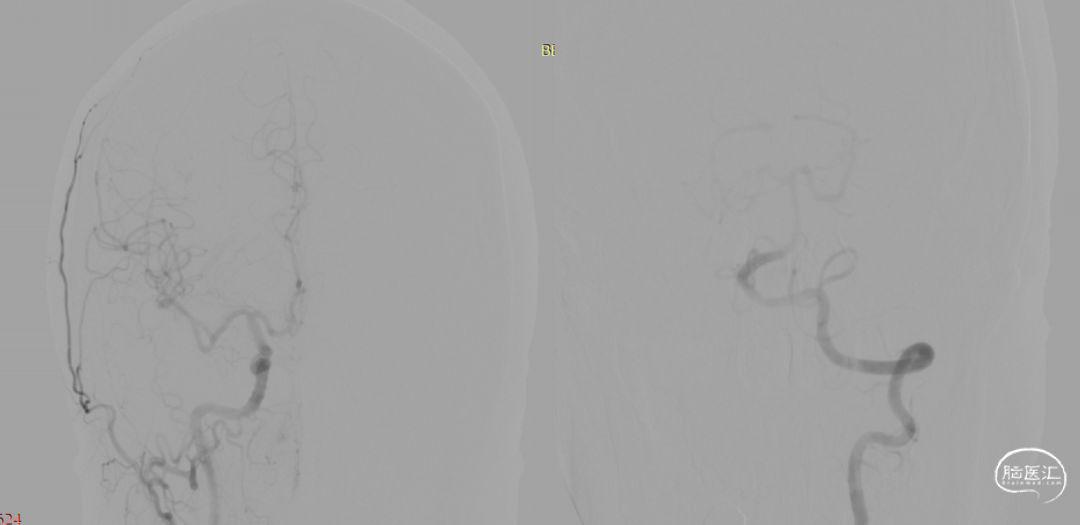

术前造影:

6F Navien到位,Phenom 27内输送J-Tube™4.25*20血流导向密网支架,顺畅到位。

头端打开良好。

J-Tube™打开过程-整体显影性能良好。J-Tube™血流导向密网支架整体释放过程,贴壁良好。

术后即刻。

术后即刻,可见动脉瘤瘤腔内血液滞留明显。

术后即刻,正侧位造影。